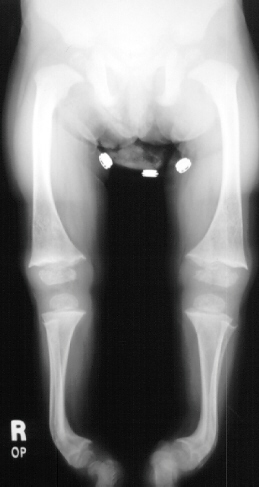

X-RAY STUDIES:

- "cupping" of the distal radius and distal femur

- widening of the physis

- angular deformities

10 months later on follow-up she had a noticeable decrease in her tibial

bowing along with almost complete resolution of the growth plate abnormalities.

At her last follow-up on March 4th 1996 (she was 4 + 4yo) she had mild

anterior lateral bowing of her tibia bilaterally with a normal thigh-foot

angle and a mechanical axis that crossed the midline of her knee.